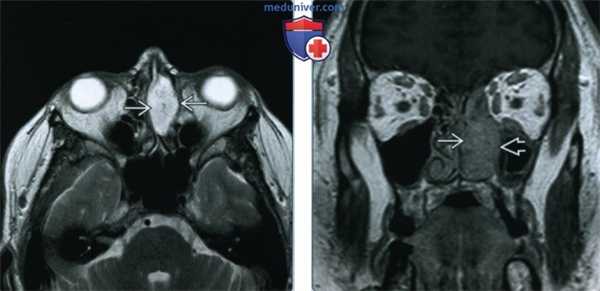

(Слева) При аксиальной МРТ Т2 в передних отделах полости носа слева определяется хорошо отграниченная, неоднородная, гиперинтенсивная доброкачественная смешанная опухоль (ДСО), происходящая из передних отделов носовой перегородки.

(Справа) При аксиальной МРТ Т1 С+ FS в передних отделах полости носа определяется ДСО, активно накапливающая контраст. Центральное контрастное усиление позволяет исключить полип носа, но лучевые признаки неспецифичны; в дифференциально-диагностический ряд необходимо включать иные неопластические процессы.

3. КТ при синоназальной доброкачественной смешанной опухоли:

• КТ без КУ:

о Хорошо отграниченное мягкотканное образование в передних отделах полости носа, исходящее из носовой перегородки

• КТ с КУ:

о Вариабельное контрастирование, неравномерное в больших опухолях

• Костная КТ:

о Ремоделирование, а не деструкция костей

4. МРТ при синоназальной доброкачественной смешанной опухоли:

• Т1 ВИ:

о Хорошо отграниченное гипоинтенсивное образование

• Т2 ВИ:

о Типичен крайне гиперинтенсивный (Т2) сигнал:

- Неоднородный сигнал в больших опухолях

• Т1 ВИ С+ FS:

о Небольшие опухоли равномерно накапливают контраст

о Большие ДСО контрастируются неравномерно

(Слева) При корональной костной КТ в полости носа справа определяется хорошо отграниченная ДСО, прилежащая к носовой перегородке. Определяется смещение кнаружи и ремоделирование латеральной стенки носа, типичное для доброкачественных процессов.

(Справа) На эндоскопической фотографии в передних отделах полости носа определяется хорошо отграниченная округлая ДСО, происходящая из передних отделов носовой перегородки.